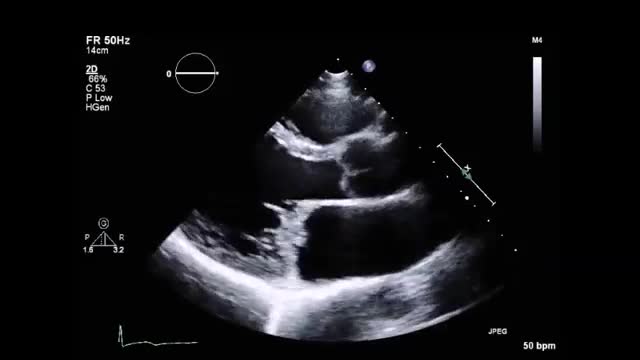

• 症例12 70代女性.収縮性心膜炎

• 図5 心エコー、手術所見 a